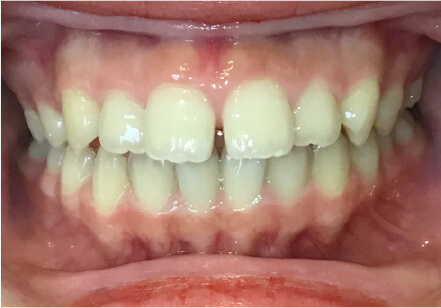

叢生の症例

8歳

女性

相談内容

前歯がでている、前歯が噛み合っていない

カウンセリング・診断結果

上下叢生、顎が狭いのでクリアコレクトで拡大配列+トレーニングで進めてく

治療内容・方法

全額アライナー矯正 クリアコレクト

術後の経過・現在の様子

リンガルアーチ使用

治療のリスク

痛み・歯根吸収・歯肉退縮・虫歯・後戻り

費用・治療期間

924,000円、8ヶ月